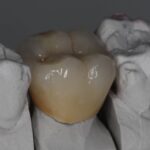

E-Max

L’E.max®, 100% céramique, est à base de disilicate de lithium, reconnu pour sa haute résistance à la flexion (500 Mpa).

Elle est donc une alternative esthétique aux restaurations céramo-métalliques, conservant, ensemble, éclat et durabilité.

Couronne, bridge de 3 éléments, inlay, onlay, facette